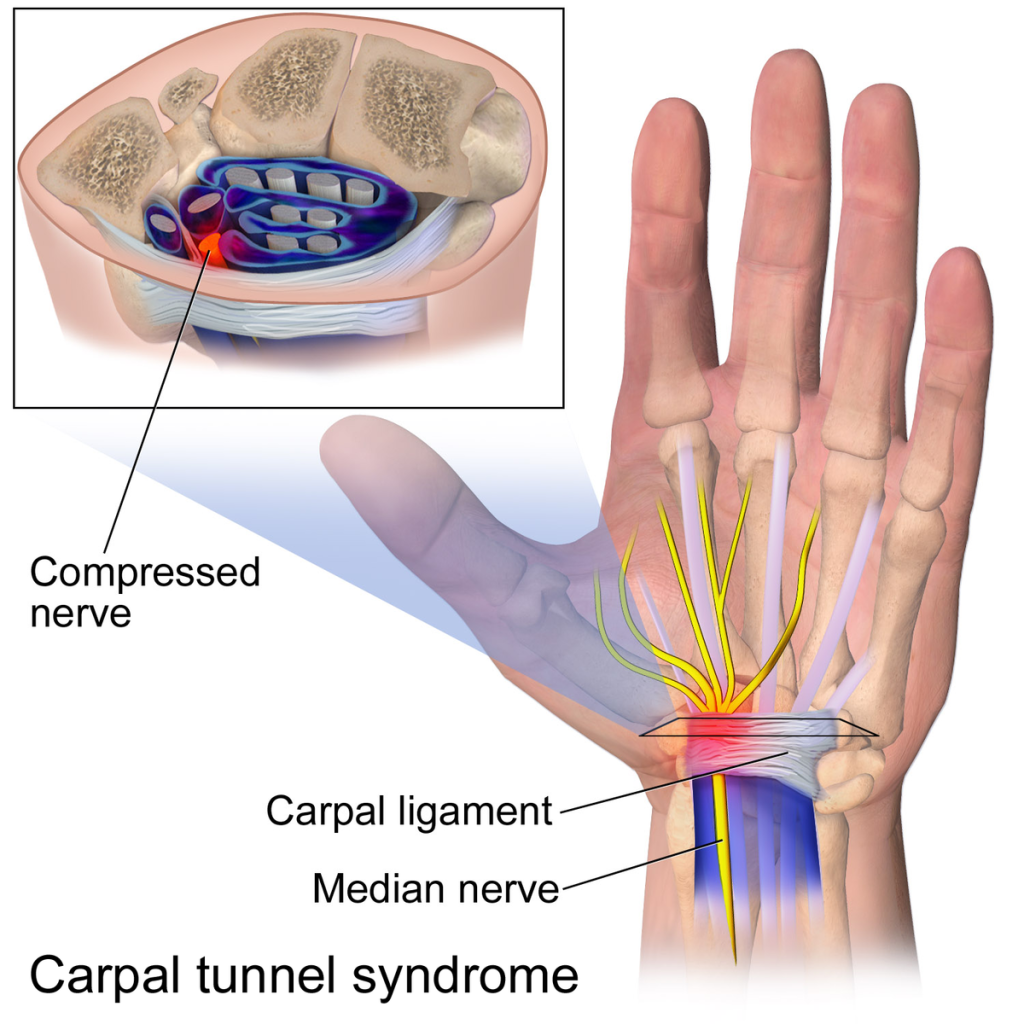

Carpal Tunnel: The median nerve in the wrist contracts, due to over exertion, which results in a tingling and sometimes numb sensation in the thumb, index and ring finger. In extreme cases, the patient experiences great pain and swelling which requires a few weeks of healing time.

Image used under Creative Commons Licensing: Carpal Tunnel Syndrome.png